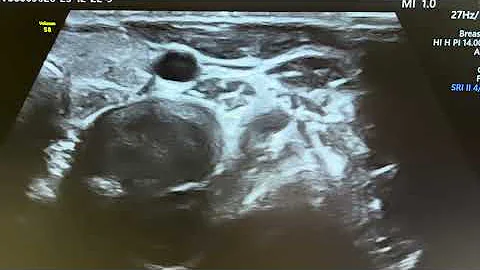

Doppler Scan (28 Weeks) | Dr. Sidhartha Sharma – Interventional & Clinical Radiologist

Hi, I'm Dr. Sidhartha Sharma, an Interventional & Clinical Radiologist at DG Diagnostics. In today's video, we'll be talking about ...